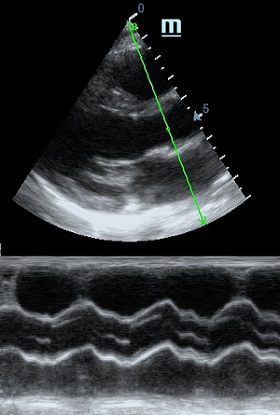

Оценка кооптации нижней полой вены ещё никогда не была такой простой и точной, никаких лишних деталей, просто устанавливаем клипер по анэхогенному участку.

Оценка сокращения сегментов левого желудочка на глаз постепенно уходит в прошлое. Если в приборе нет функции радиального или лонгитудинального стрейна, на помощь опять может прийти Free Xros. Утолщение более 5 мм в систолу – нормальное сокращение, 2-5 мм гипокинез, истончение в систолу – дискинез.